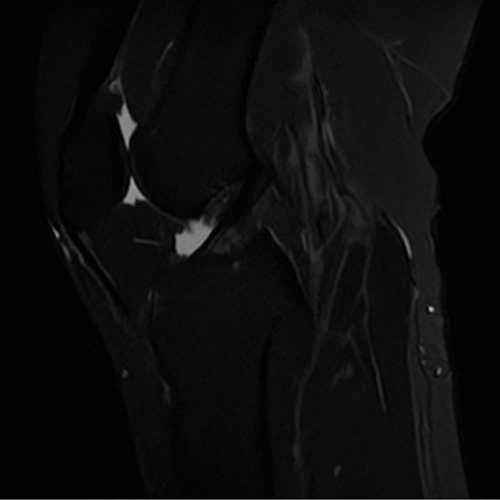

MRI検査

装置の紹介

当院では1.5テスラ キヤノンメディカルシステムズExcelart Vantage (MRT-2003)を用いています。

この装置は撮像時の騒音が従来装置に比べ約90%低減されています。また、検査架台の長軸が短縮され解放的でリラックスして検査を受けることができます。

MRI検査とは

CTやX線検査と違い、磁石と電波を使って体の様々な断面像を撮像するので、放射線による被ばくはありません。

造影剤を使用せずに血管を描出することもでき、脳動脈瘤や血管狭窄などの診断に利用されます。また、胆管・膵管・脊髄・尿路なども非造影で検査を行うことができます。

頭部検査においては、特に有用で、CT検査では発見できない急性期の脳梗塞を捉えることができ、早期診断・早期治療を可能にします。この他にも、脊椎・骨軟部・関節・腹部・骨盤腔(子宮・卵巣・前立腺)の病変に優れた描出能があり、様々な疾患の早期発見・診断に有用とされ、研究が進んでいます。

全身DWI

頭部

脳血管像(非造影)

胆管・膵管(非造影)

腹部

乳房DWI